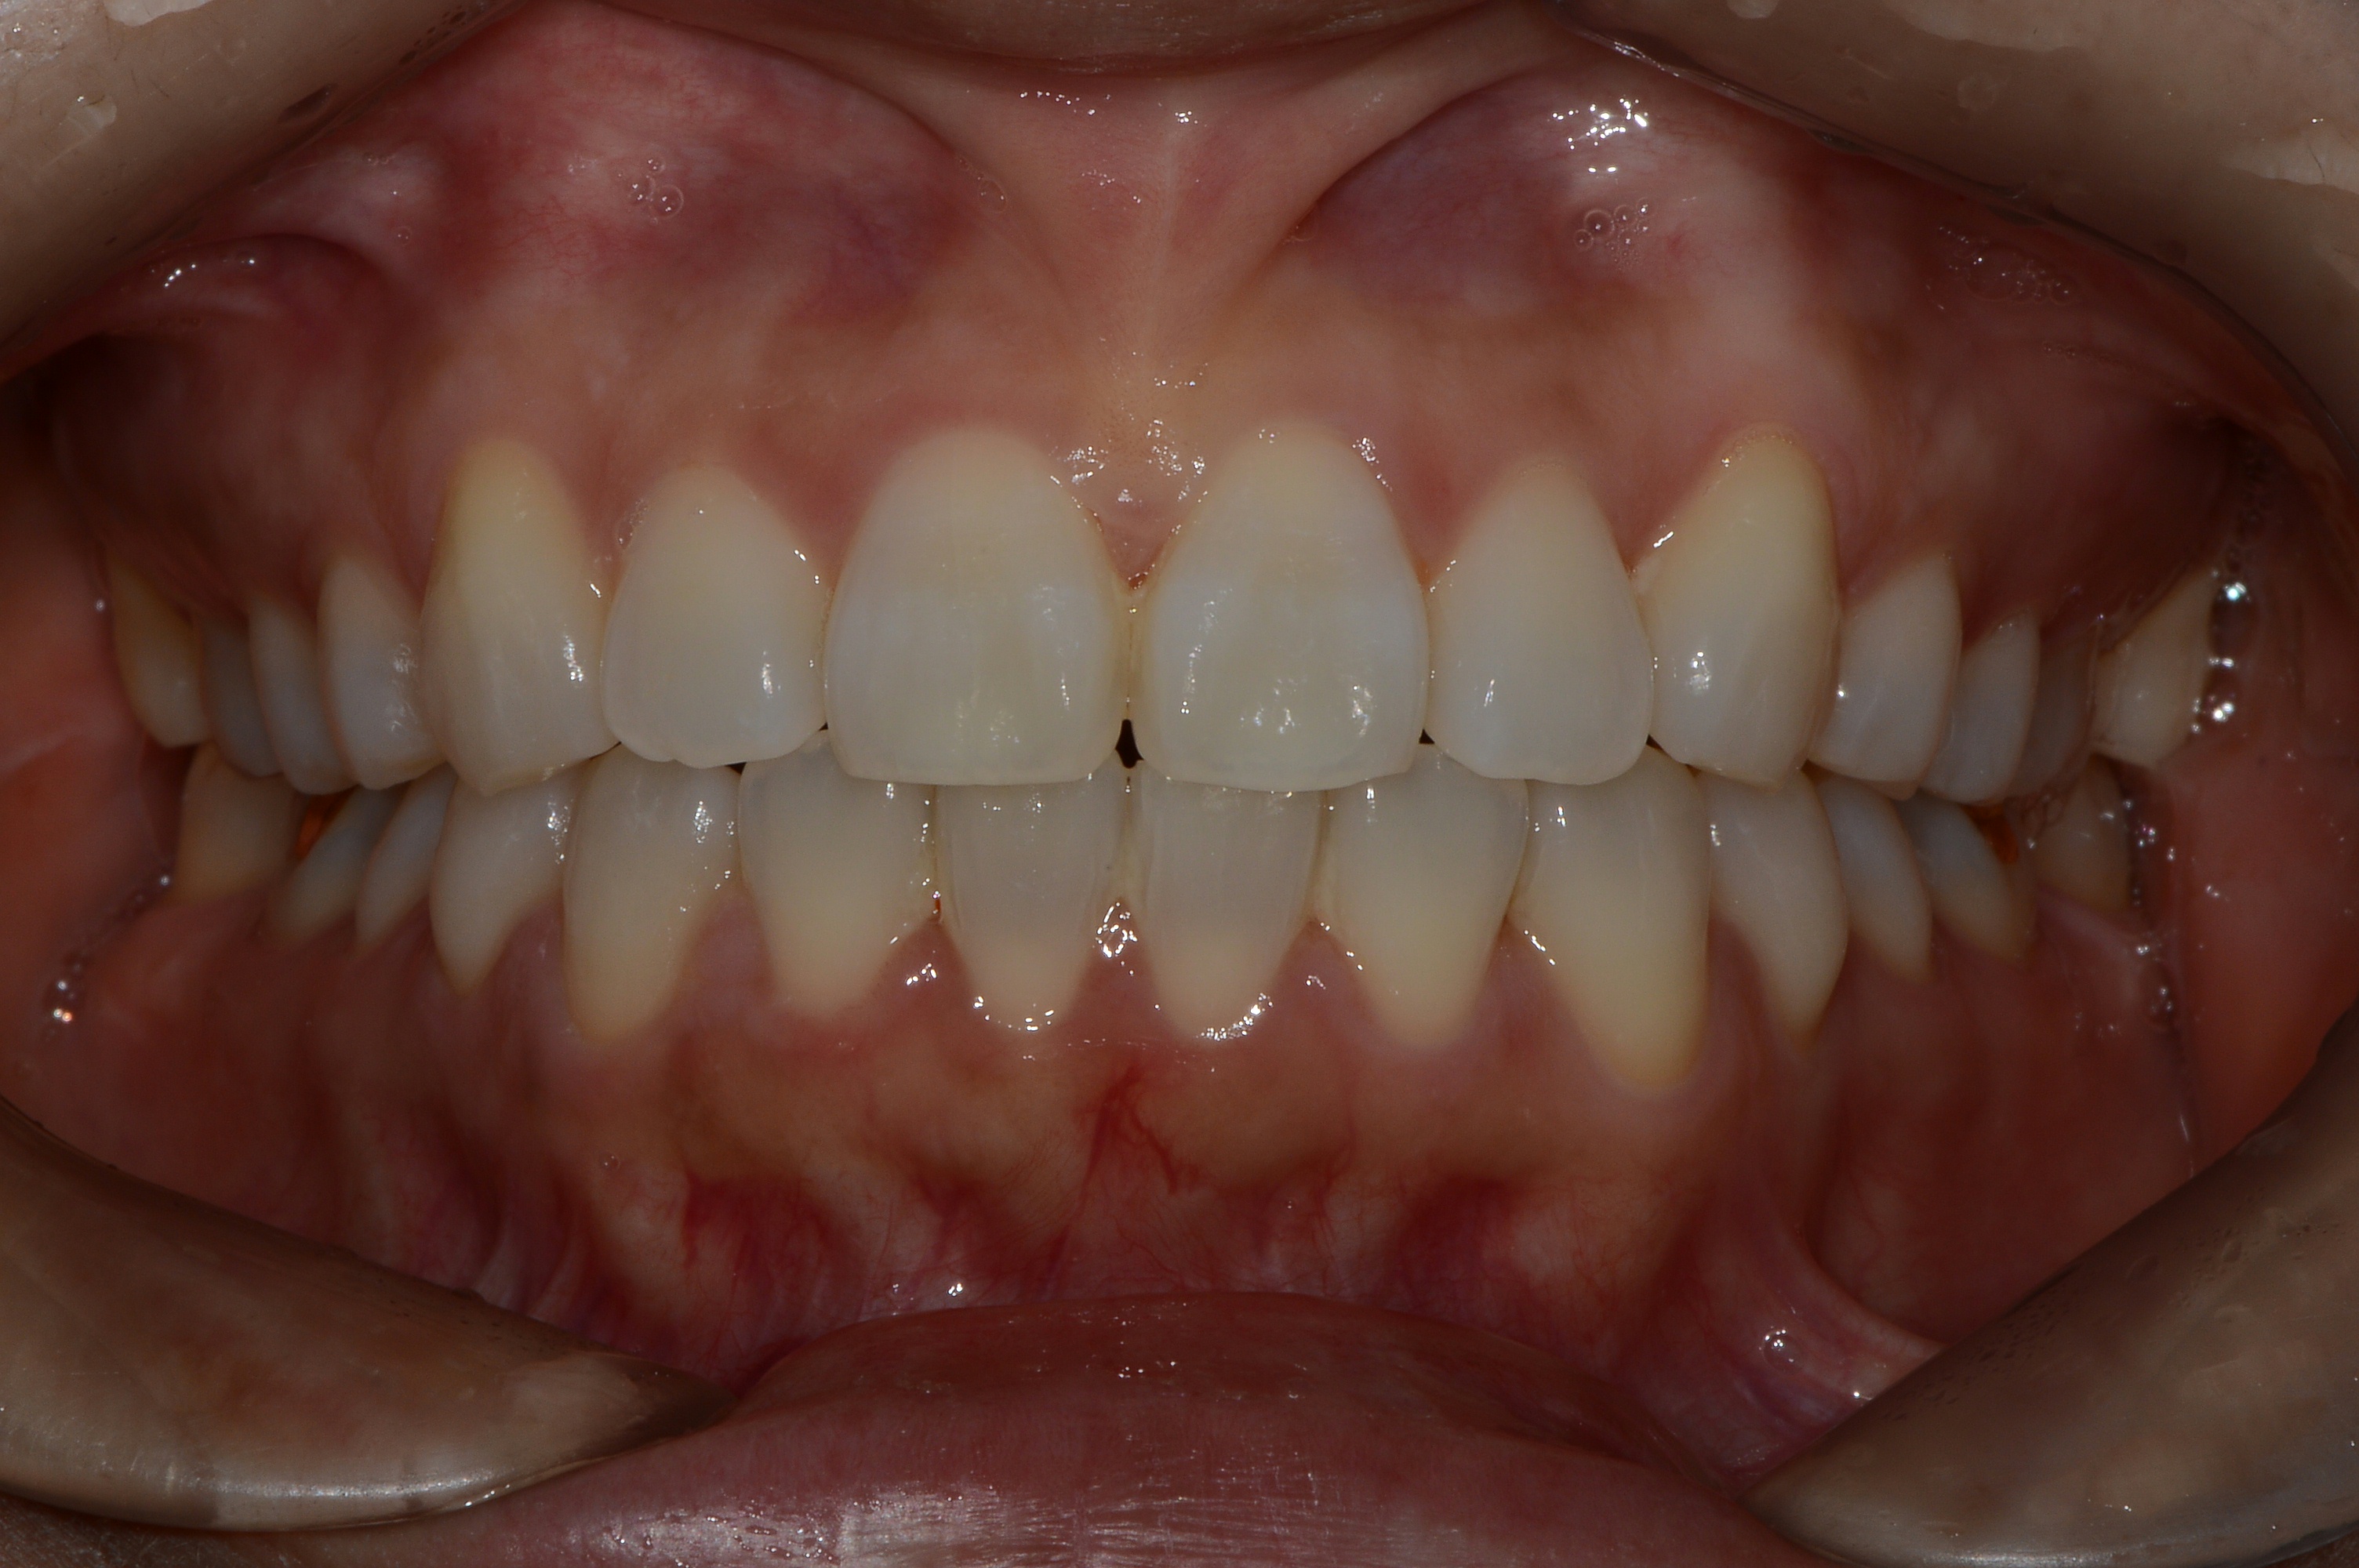

치료 후 사진입니다.